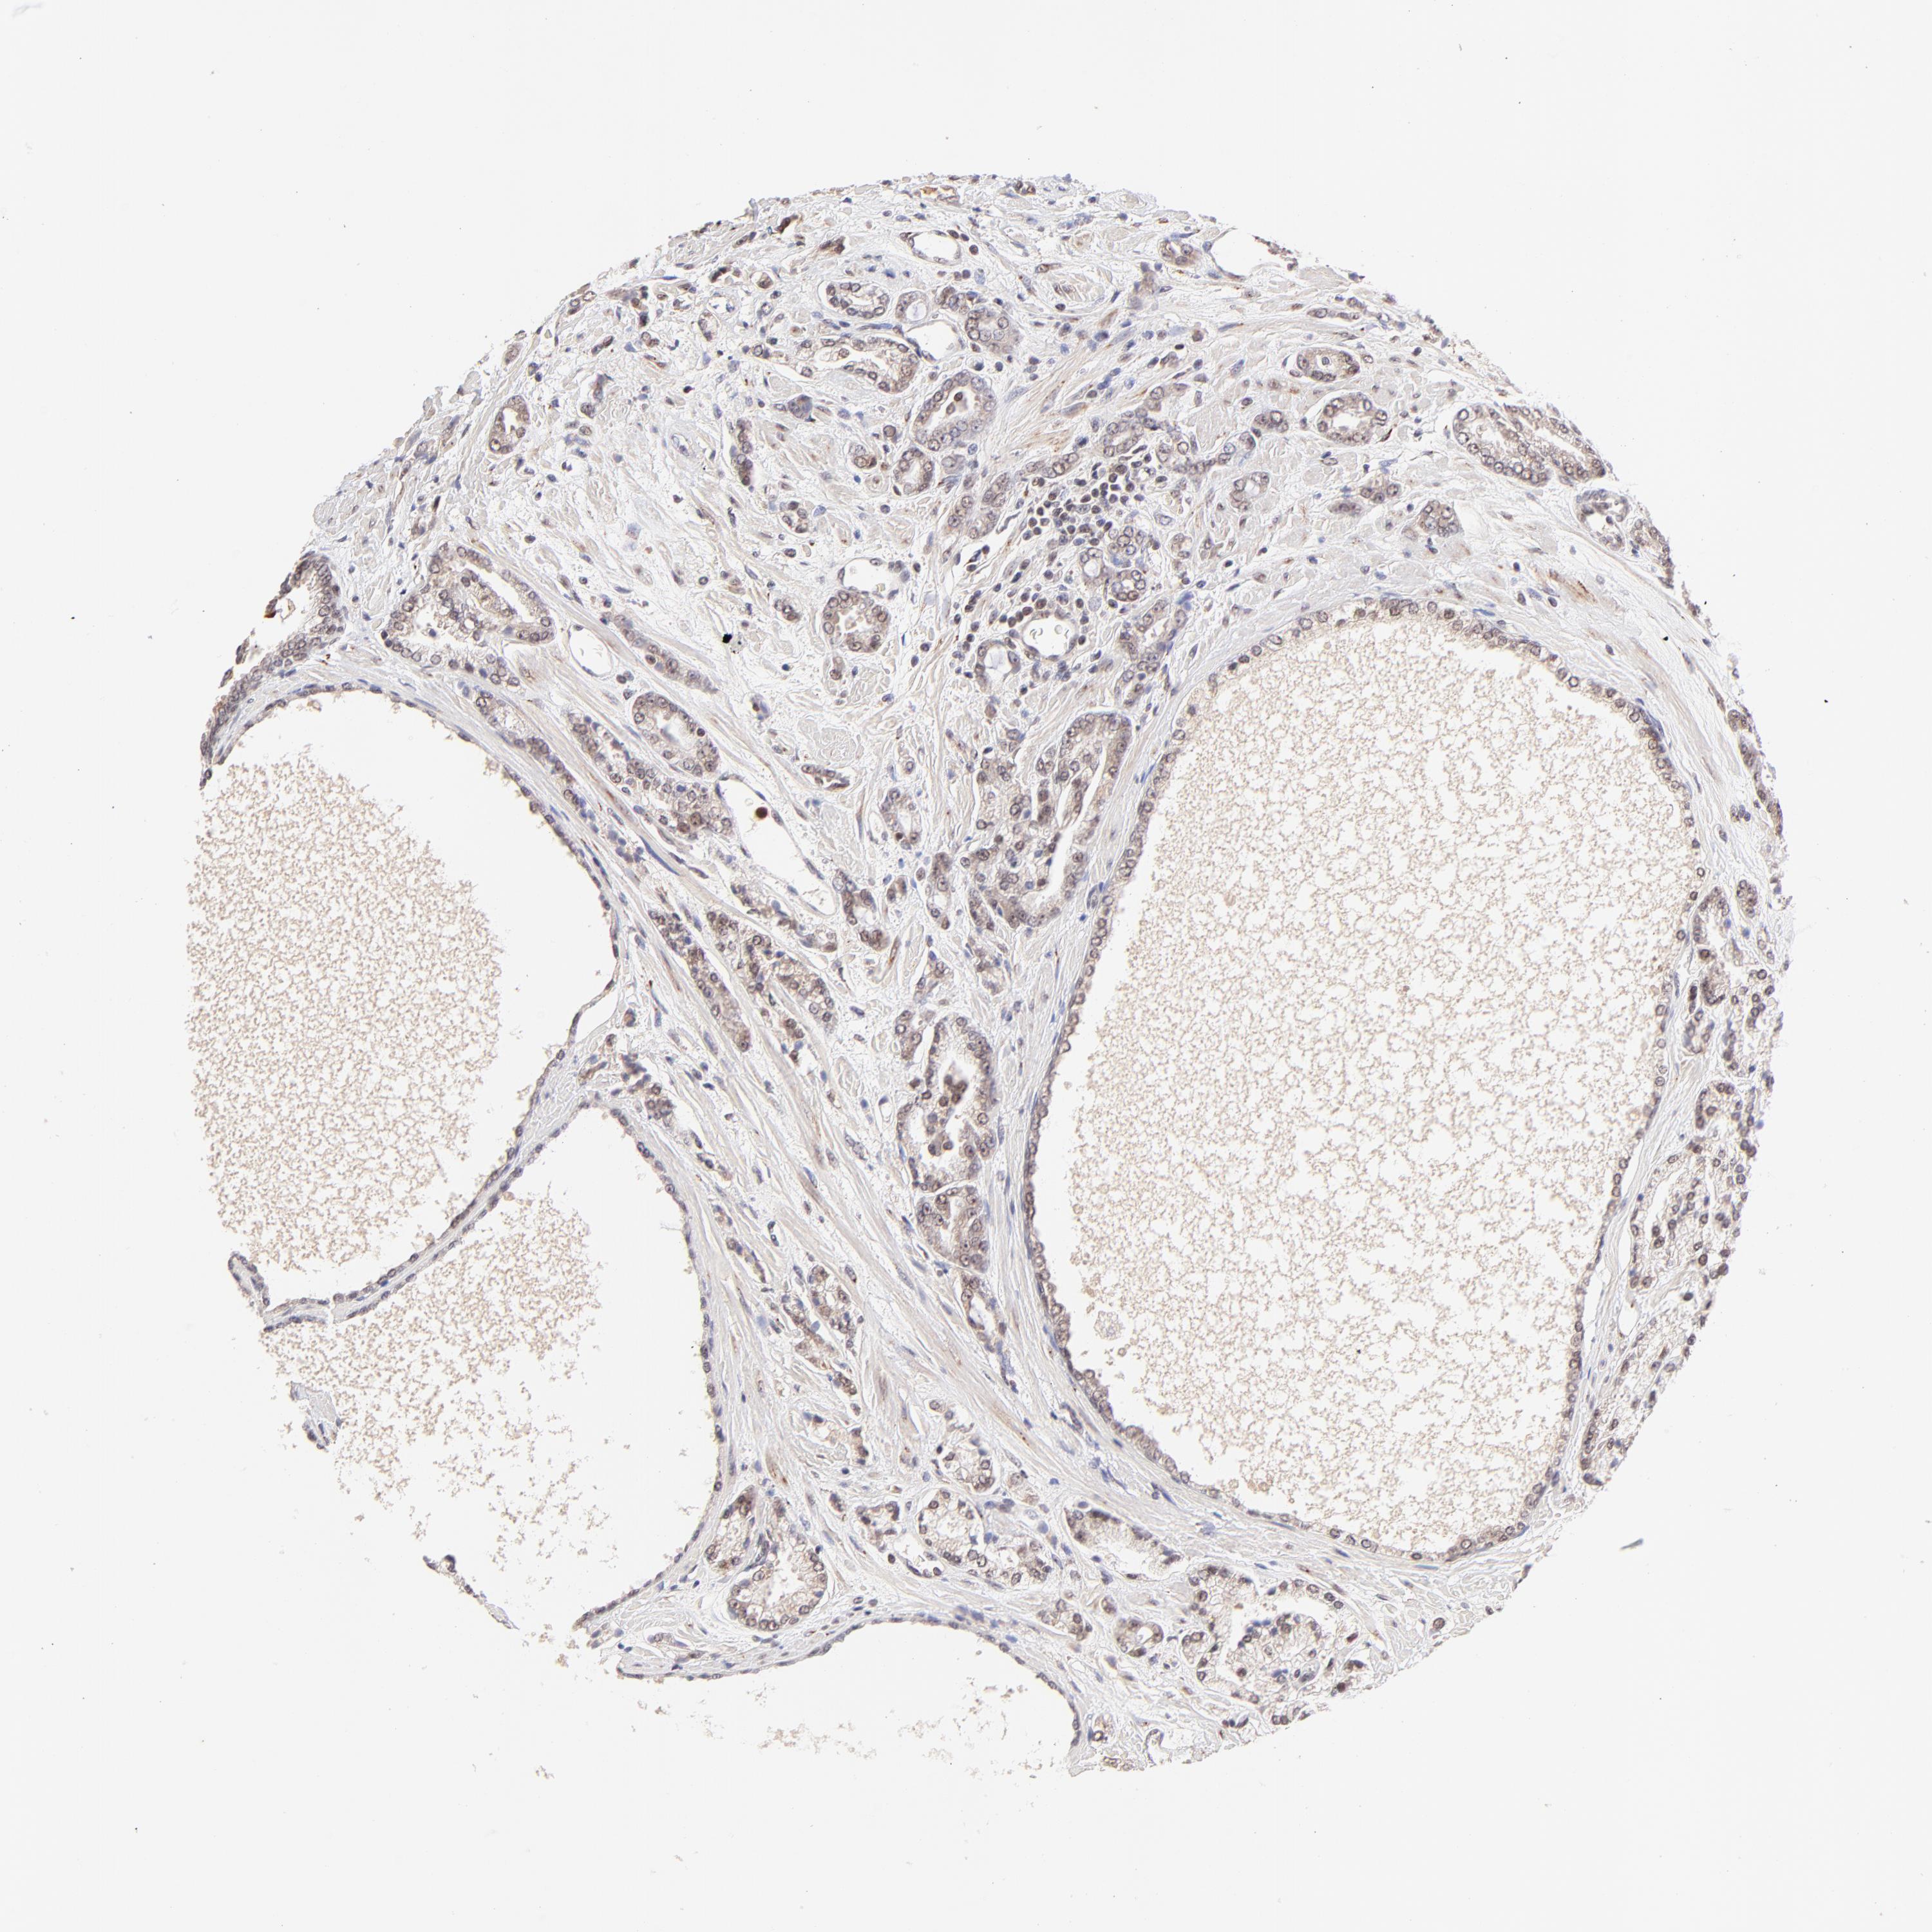

PROSTATE CANCER - Protein expressioni

A mouse-over function shows sample information and annotation data. Click on an image to view it in a full screen mode. Samples can be filtered based on level of antibody staining by selecting one or several of the following categories: high, medium, low and not detected. The assay and annotation is described here.

Note that samples used for immunohistochemistry by the Human Protein Atlas do not correspond to samples in the TCGA dataset.

Antibody stainingi

Antibody staining in the annotated cell types in the current human tissue is reported as not detected, low, medium, or high, based on conventional immunohistochemistry profiling in selected tissues. This score is based on the combination of the staining intensity and fraction of stained cells.

Each image is clickable and will lead to virtual microscopy that enables deeper exploration of all samples and also displays staining intensity scores, fraction scores and subcellular localization as well as patient and tissue information for each sample.

Antibody HPA003184

Antibody HPA003185

Staining

High

Medium

Low

Not detected

Intensity

Strong

Moderate

Weak

Negative

Quantity

>75%

75%-25%

<25%

None

Location

Nuclear

Cytoplasmic/membranous

Cytoplasmic/membranous,nuclear

Adenocarcinoma, Low grade

Adenocarcinoma, Medium grade

Adenocarcinoma, High grade